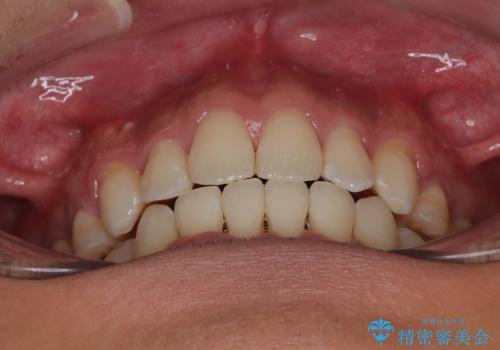

- 前歯のデコボコ(叢生)と、少し前に出た口元を気にされて来院された患者さまです。

診査の結果、上下顎ともに歯が並ぶスペースが不足しており、上下の前歯が噛み合わない**オープンバイト(開咬)**の状態でした。

歯をすべて並べようとすると口元がさらに前に出てしまうため、上下左右の第一小臼歯を抜歯してスペースを確保し、デコボコと突出感の両方を改善する治療計画を立てました。